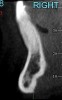

CASE 2 Fig 4. Post-orthodontic Miller Class II recession for which orthodontic treatment was not recommended. Clinical view 3 years after orthodontic treatment, showing relapse in teeth alignment and GR on lower left central incisor.

Figure 4

Fig 5. CBCT sagittal view of the same patient showing thin/no bone on the lingual aspect.

Figure 5

In cases with thin lingual bone, as measured on CBCT (<2.5 mm at a level of 8 mm apical to the CEJ), orthodontic treatment is not advisable, leaving surgical root coverage as the only option. However, the prognosis for this procedure is poorer, because the predominant cause is not addressed. Figure 4 shows the frontal clinical view of a patient with a hyperdivergent growth pattern who presented with post-orthodontic GR of a labially displaced lower central incisor. The sagittal CBCT view (Figure 5) shows complete absence of lingual bone, which contraindicated orthodontic tooth repositioning.